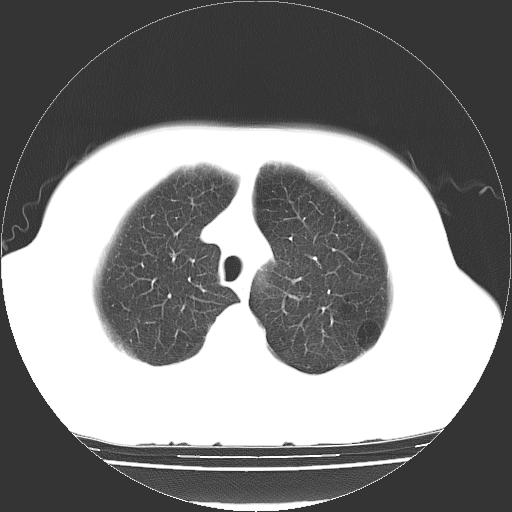

标题: CT13141:女,70岁,咳嗽、胸闷半个月。 [打印本页]

标题: CT13141:女,70岁,咳嗽、胸闷半个月。

女,70岁,咳嗽、胸闷半个月。纵隔窗未见异常,未上传。

慢支炎、肺气肿征,双肺多发肺大泡

小叶中心型肺气肿并多个肺大泡形成。

小叶中心性肺气肿及间隔旁肺气肿.(多与吸烟有关)